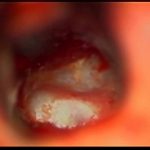

'14年10月

40代

海綿状血管腫

No.’14_160 手術前1

No.’14_160 摘出 前

No.’14_160 摘出 後